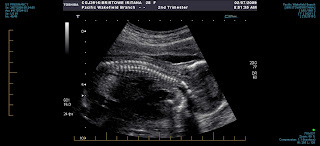

Picture time!!!

Image

Evening everyone!!! We thought it would be nice to give you all a bit of an idea where our "little" baby is hanging around these days. Baby is still very much active and Tana can actually feel foots and hands so you can imagine the extensive growth the little man is going through. But let's not keep you in suspense any longer, let me introduce... Tuwhakairiora This is a great angle and you can really see how the baby is getting comfortable, you can see even better in the next shot. For those of you that noticed the name of our boy and went like "uhhh WHA??? how do you say that?!?" we will be having tiny lessons every now and again to help you say it, took me only one night and some trial and error like activity but I REALLY like the name a lot and I am sure you will like it just as much... and you can always do the same as you do with me, shorten it to something quick and easy... Tu! Lots of love and keep you posted. Bo, Tana & Tu